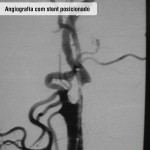

Estenose da artéria renal

O que é

Estreitamentos das artérias dos rins – levam sangue e ajudam os rins a filtrar o sangue e também a controlar a pressão arterial por auxiliar a secretar o hormônio renina – que impedem o órgão de trabalhar corretamente.

Diagnóstico

É feito com base no exame clínico e em exames complementares como ultrassom abdominal (mostra os vasos sanguíneos e o órgão e facilita a localização de coágulos ou áreas de estreitamento e a determinação do tamanho do rim), ecografia vascular com Doppler (analisa precisamente o fluxo sanguíneo renal e estima o grau de estreitamento das artérias renais), angiotomografia computadorizada (revela com precisão a estrutura da parede dos vasos sanguíneos de médio e grosso calibres), angioressonância magnética (produz imagens bi ou tridimensionais das estruturas internas do órgão), angiografia (localiza os estreitamentos ou a obstrução através de raio-x) e cintiolografia renal (analisa o fluxo sanguíneo nos rins).

Tratamento

Inicialmente, o especialista utiliza medicamentos, mas quando o uso é ineficiente, levando à perda da função renal, recomenda-se a angioplastia renal.

Angioplasita renal

Técnica cirúrgica minimamente invasiva indicada, basicamente, para casos de estenoses críticas (acima de 70%) de uma ou de ambas as artérias renais com comprometimento da função dos rins.

Como funciona

Todo o procedimento é realizado “por dentro dos vasos sanguíneos”, através de uma punção na região da virilha. Não há cortes ou necessidade de pontos. Uma anestesia local é empregada junto com uma sedação leve.

São introduzidos cateteres até o vaso acometido através do qual é implantado um stent (tubo metálico que mantém o vaso aberto), que é expandido por um balão. A taxa de sucesso do procedimento é de 95%, ou seja, em apenas 5% das vezes não é possível implantar o stent.

Fotos